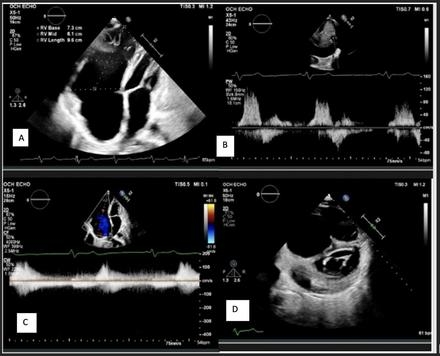

Clinical examination revealed signs consistent with chronic venous congestion, including bilateral lower extremity edema and elevated jugular venous distention. Echocardiography assessment demonstrated preserved left ventricular ejection fraction (65%), markedly dilated right atrium and ventricle (ventricularization of the right atrium), absence of the tricuspid valve, and elevated central venous pressure. Due to underlying COPD, initial respiratory management led to clinical improvement, and the patient was discharged for outpatient cardiopulmonary follow-up. We decided against valve replacement during his clinic visit, given his medical history and ability to perform all daily activities independently without any symptoms.